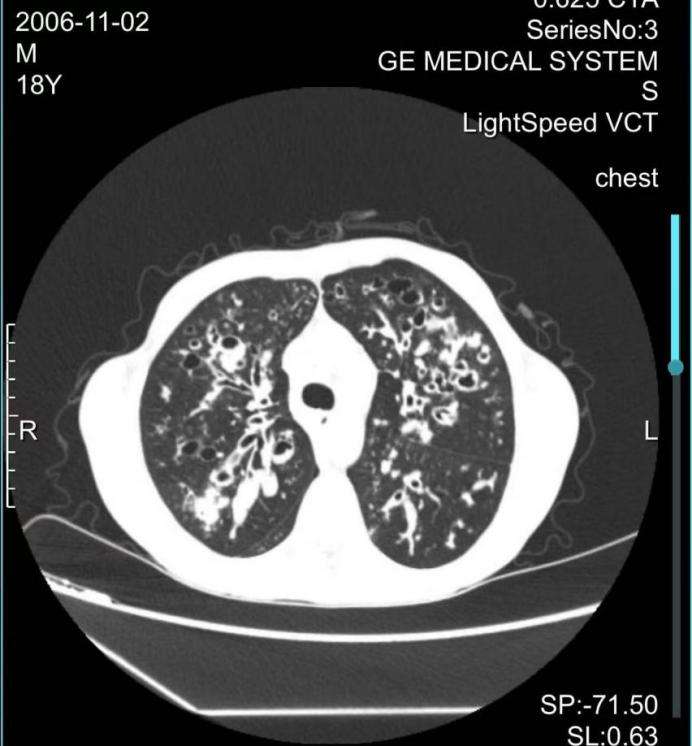

患儿肺囊性纤维化伴感染的ct影像

首例患者为2岁患儿小宇(化名),多次重症肺部感染伴胃食管反流,导致肺部炎症迁延不愈。经噬菌体雾化治疗72小时后,痰培养转阴,感染得到完全控制。第二例为18岁患罕见病囊性纤维化的小金(化名),多次因重症肺炎、呼吸道感染至多家医院治疗,本次在上海市儿童医院确诊为肺部多重耐药铜绿假单胞菌感染,在药物治疗重重受阻的情况下,通过支气管镜注入噬菌体,成功开展肺囊性纤维化合并多重耐药铜绿假单胞菌感染的重症患者噬菌体治疗,为患者后续进一步治疗带来希望。